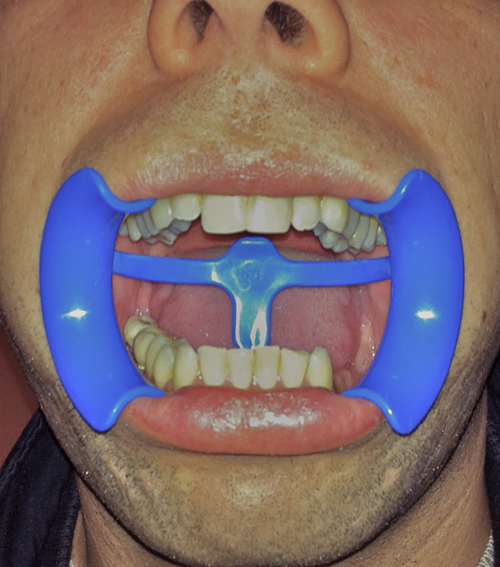

Palabras Clave: ELG: Estereolitográfico OH: Oclusión Habitual ORC: Oclusión en Relación Céntrica Paciente de 35 años de edad ,sexo masculino que lo derivan para implantar el tercer cuadrante. A la auscultación presenta ruidos articulares de tipo chasquido que remiten temporalmente luego de limitación de apertura bucal y maniobras quinesiológicas distractoras. También se observan recidivas de caries en algunos empastes y falta de disclusión canina de ambos lados. Se estudia el caso desde un punto de vista clínico, scanografico mediante Dentascan y tridimensional mediante montaje en articulador. A partir del scanner se obtienen datos para confeccionar modelo estereolitográfico (ELG),operar en el y construir férula quirúrgica dento-muco soportada. Habitualmente se procede directamente a implantar, dado que ese era el requerimiento del profesional derivante y el deseo del enfermo. Sin embargo, esa actitud enmascararía otro tipo de problemas que la boca presenta. Se consulta al odontólogo derivante, y coincide con mi opinión acerca de que si solo se lo implanta, sin corregir la posición mandibular, la situación de las ATMs, los empastes sin anatomía y la falta de disclusiones, el resultado final no será el deseado y su eficacia masticatoria no funcionará optimamente. Consultado el paciente coincide y acepta ese concepto y entonces procedemos a confeccionar un Jig de Lucia a partir del montaje de estudio, y lo dejamos puesto en boca toda la noche anterior a la consulta, para proceder a realizar un ajuste oclusal al día siguiente sin engramas anteriores, lo que facilita no tener que relajar nuevamente con laminillas de Long. En esta etapa pierde el implante correspondiente a la pieza 4.7 que traía en boca. Estabilizado el sistema, procedemos a la parte quirúrgica, comenzando por instalar la férula, retirar opérculos gingivales mediante bisturí circular, fresado óseo e instalación de implantes ,toma de impresión a cubeta fenestrada (pegando con metacrilato sin cambios dimensionales, los transfers a la cubeta especialmente diseñada.(1º método de pasividad protética utilizado), e instalación de tornillos de cicatrización. Inmediatamente de retirada la cubeta de boca y colocadas las réplicas de los implantes, procedemos a ferulizar los “ápices” de las réplicas para que no sufran movimientos durante el llenado de la impresión.(2º método de pasividad protética utilizado). Controlamos radiograficamente Tres meses después, procedemos a tomar nuevos registros de arco facial, registros intermaxilares en Oclusión en Relación céntrica, montaje de los modelos obtenidos intra operatoriamente y confección de un conjunto de cuatro coronas provisionales de metacrilato en el sector implantado y las correspondientes al maxilar superior. Verificada la perfecta función de todos los componentes, ausencia de todo tipo de síntoma y comprobada la paz en todo el sistema, procedemos tiempo después a confeccionar las fundas definitivas, que constituyen el “cerrojo” de la dinámica del mismo. Por último, corroboramos la oclusión fundamentalmente en lo que hace a la: